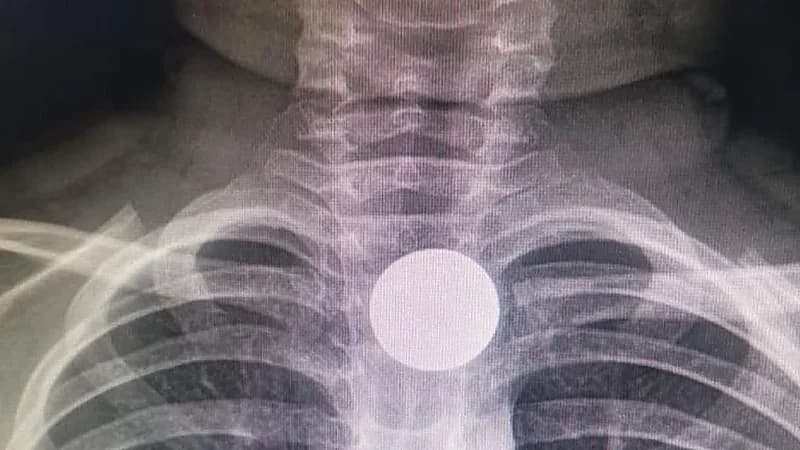

استطاع الفريق الطبي بمستشفى الخفجي العام أحد مكونات تجمع الشرقية الصحي، من انقاذ حياة طفل ابتلع قطعة معدنية.

وفي التفاصيل، استقبل قسم الطوارئ بالمستشفى طفل يبلغ من العمر ٦ سنوات، قام بابتلاع قطعة معدنية، علقت في أعلى المريء، مما أدت إلى عدم القدرة على البلع.

وعلى الفور قرر الفريق الطبي إجراء عملية عاجلة لاستخراج القطعة المعدنية، وذلك تحت التخدير العام وتمت العملية بنجاح دون حدوث مضاعفات، ومن ثم غادر الطفل من المستشفى وهو بصحة جيدة.